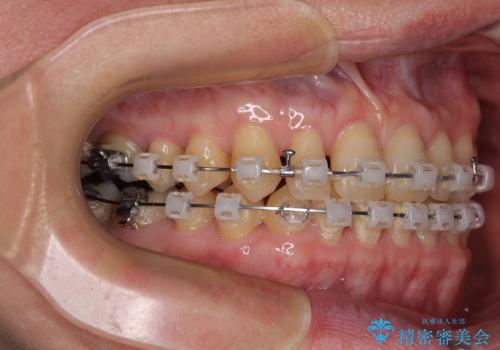

- 矯正装置

- クリアブラケット

- 前歯のデコボコと隙間の空いた歯列を気にして来院された患者様です。

下顎前歯が隠れるほどのディープバイトにより、強い咬合力と突き上げで上顎歯列に隙間が空いている状態でした。

手前に傾斜している奥歯をワイヤー装置で立ち上がらせ、咬み合わせの高さを挙上することで突き上げを解消し、空隙歯列を改善していくこととしました。